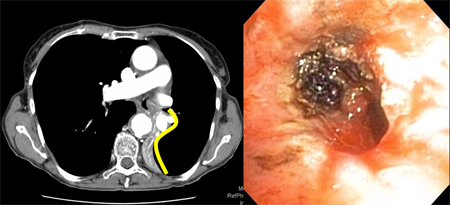

Post-lung transplant anastomotic bronchial stenosis: electrocautery radial incision

From the collections of Jose Fernando Santacruz MD, FCCP, DAABIP and Erik Folch MD, MSc; used with permission